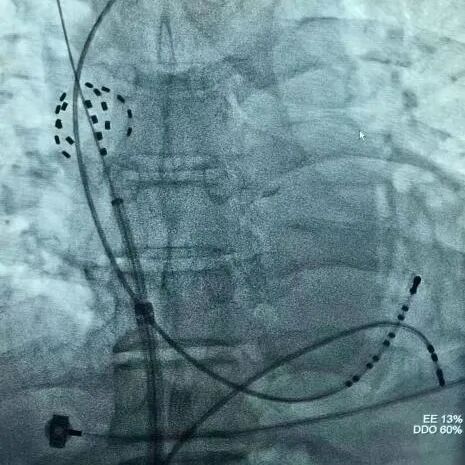

DSA下FARAPULSE导管呈花瓣状态

DSA下FARAPULSE导管呈网篮状态

2. 微创操作:单纯二维透视引导,避免额外影像辐射,最大限度降低手术创伤,计划在短时间内完成肺静脉+上腔静脉隔离;

术中,团队凭借娴熟的操作技巧,在单纯二维透视引导下,精准定位肺静脉及上腔静脉口,顺利完成脉冲消融肺静脉+上腔静脉隔离,PVI+SVC全程仅耗时25分钟。术后即刻评估显示,肺静脉及上腔静脉隔离效果理想,患者房颤症状消失,生命体征平稳,术中未发生并发症,标志着手术圆满成功。